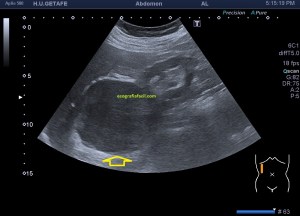

Es muy útil para lesiones que han crecido mucho y no podemos conjugar en una sola imagen, por ejemplo, un lipoma, cuando superan la medida de la huella de la sonda no son medibles, hay que usar «panoramic view», y como este caso, otros muchos.

En la imagen 3 ves una imagen de un lipoma, mide 7 cms, la huella de la sonda mide 5cms, la «panoramic view» posee una regla centimetrada que sigue el contorno de la imagen, justo en la profundidad de la misma y lo marca la flecha amarilla. La profundidad la marca la flecha roja y la flecha blanca marca el rango centimetral de los 5cms, fíjate que la línea blanca es ligeramente mayor cada 5 cms. Sirve de referencia, como en la imagen 4 donde ves una colección en el glúteo de más de 10 cms.